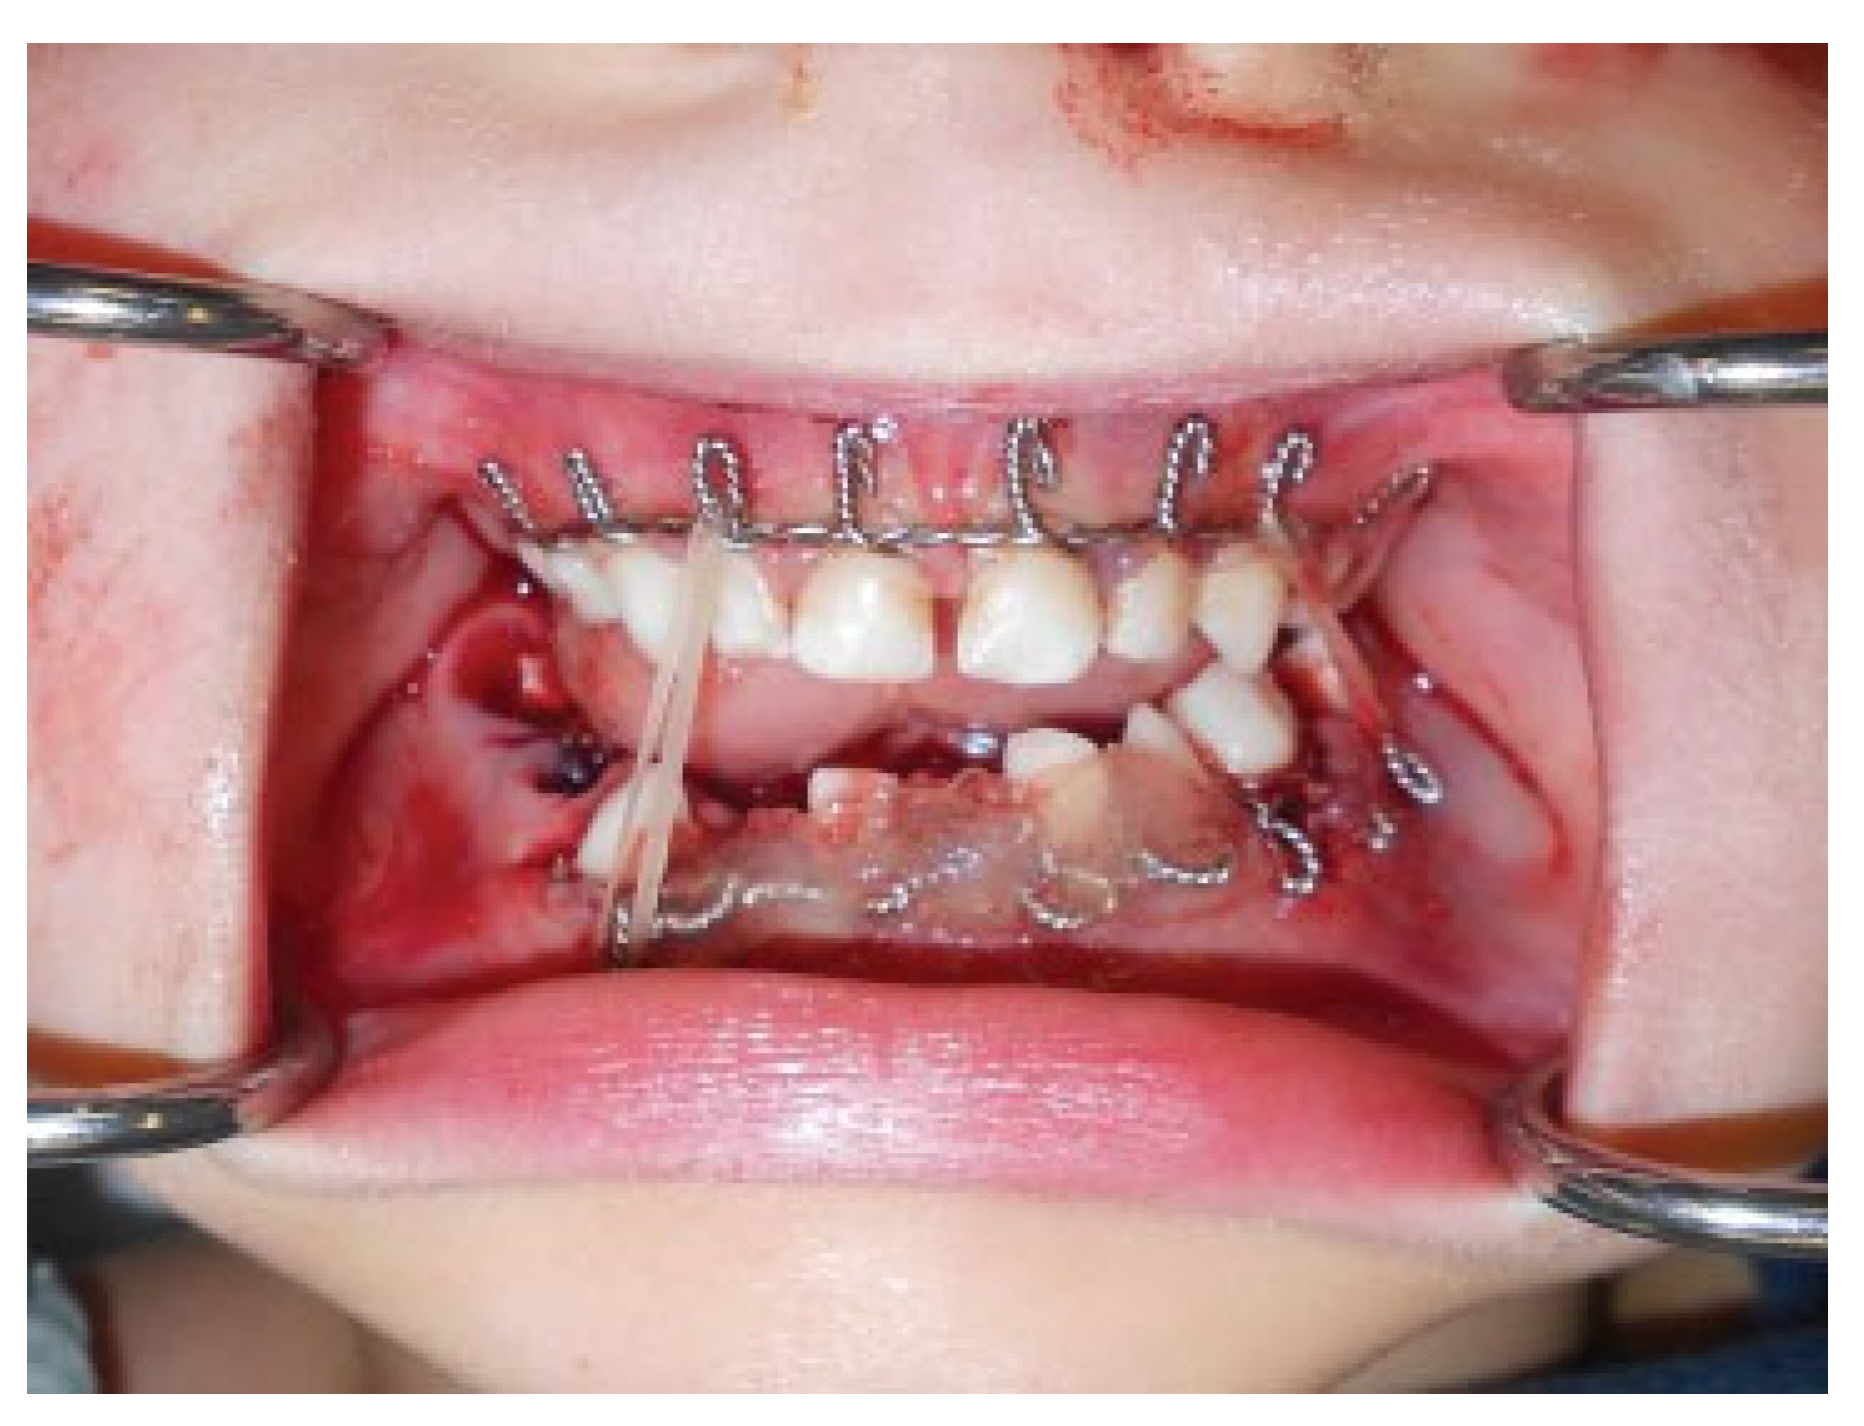

Modifications to this procedure include using 24-gauge stainless steel wire that is passed from the last molar as originally described (Figure 2). The wire is then twisted from one side of the dental arch to the other (Figure 3). Ideally, circumdental ligatures are passed to secure the individual teeth as the cable is being twisted (Figure 4). This will allow for secure fastening of the cable and ligature complex. Finally, when the wires composing the Risdon cable have reached the contralateral molar tooth, it is then secured and the final circumdental ligature is placed. The circumdental wires are cut and twisted in a traditional fashion that will allow loops for securing elastics or wiring to establish MMF or guiding functions (Figure 5). If elastics are used for MMF, it is most unusual for the Risdon wiring to pull off or otherwise fail as the elastics “give.” Aside from establishing MMF, this procedure may also be used for splinting avulsed or luxated teeth, and may be supplemented with autopolymerizing resin for stability (Figure 6). Following application of the Risdon cable, open reduction internal fixation may then be performed with the patient in MMF (Figure 7).

Figure 6. Stabilization of both cable and teeth using autopolymerizing resin.